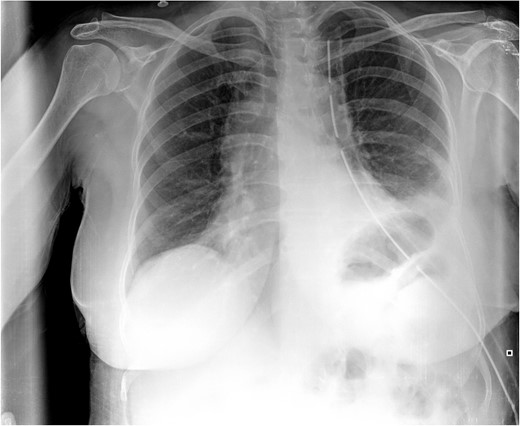

Computed tomography (CT) scan showed a cystic formation containing varying densities. The cyst size was 15 × 13 × 12 cm with an ambiguous location involving the left lower thorax and the left hypochondrium, with a direct bordering of the pericardium and the left hepatic lobe (Fig. 1).

Computed tomography (CT) scan. (A) Coronal section, shows the cystic formation in the left hemi-thorax. (B) and (C) Axial section, shows the borders with the pericardium and the left hepatic lobe. (D) Sagittal section, shows the limited posterior extension of the cyst.